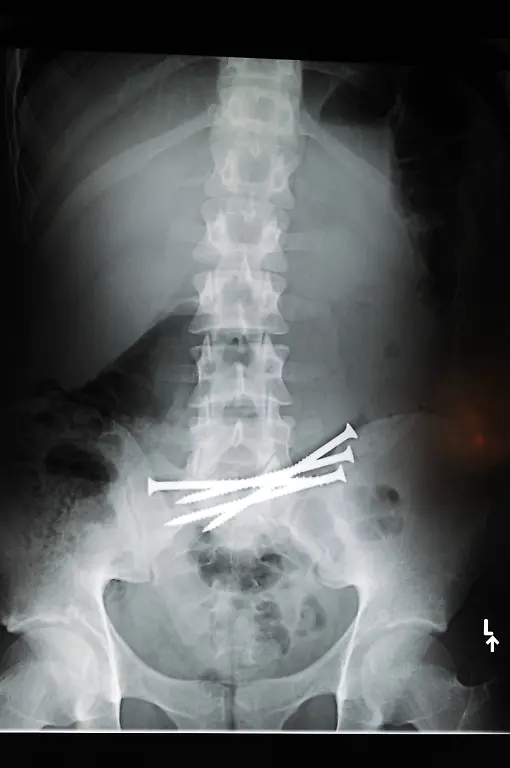

Nägel, Messer, TelefoneWas Röntgenstrahlen zum Vorschein bringen

Nicht immer zeigen Röntgenaufnahmen das, was man von ihnen erwartet. Oft kommt es zu Bildern, die selbst hartgesottene Betrachter zum Schaudern bringen - und der Wissenschaft Rätsel aufgeben.